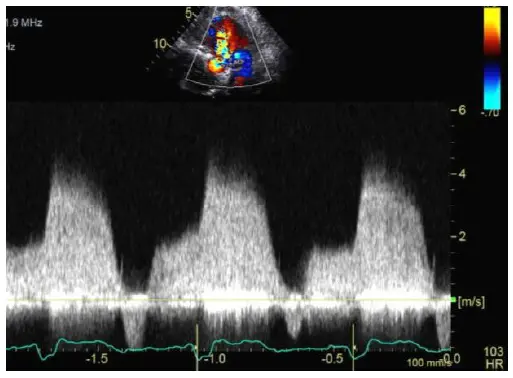

Pressure Half Time (PHT)

Mitral Valve Area (MVA) from PHT

In the above Doppler tracing, is 2 m/s. This example also illustrates the ‘a-dip’ that can sometimes be seen with Aortic Regurgitation.